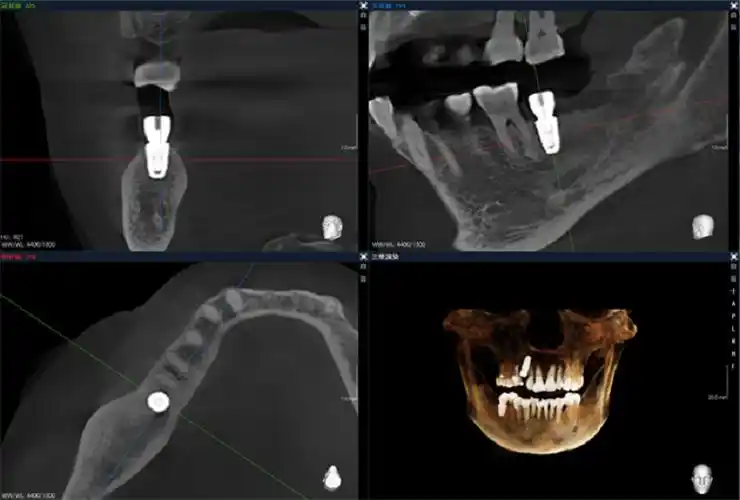

博爵ct国产大视野智能口腔cbctai引领口腔门诊数字化发展